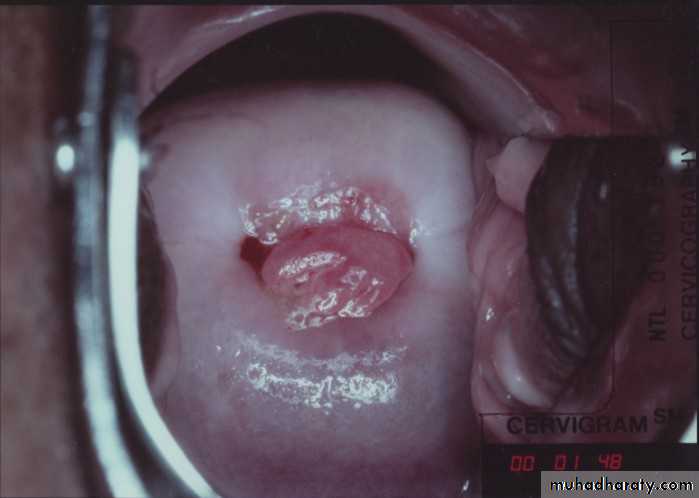

cervicitis.Polycystic ovary disease

Cervical carcinoma.